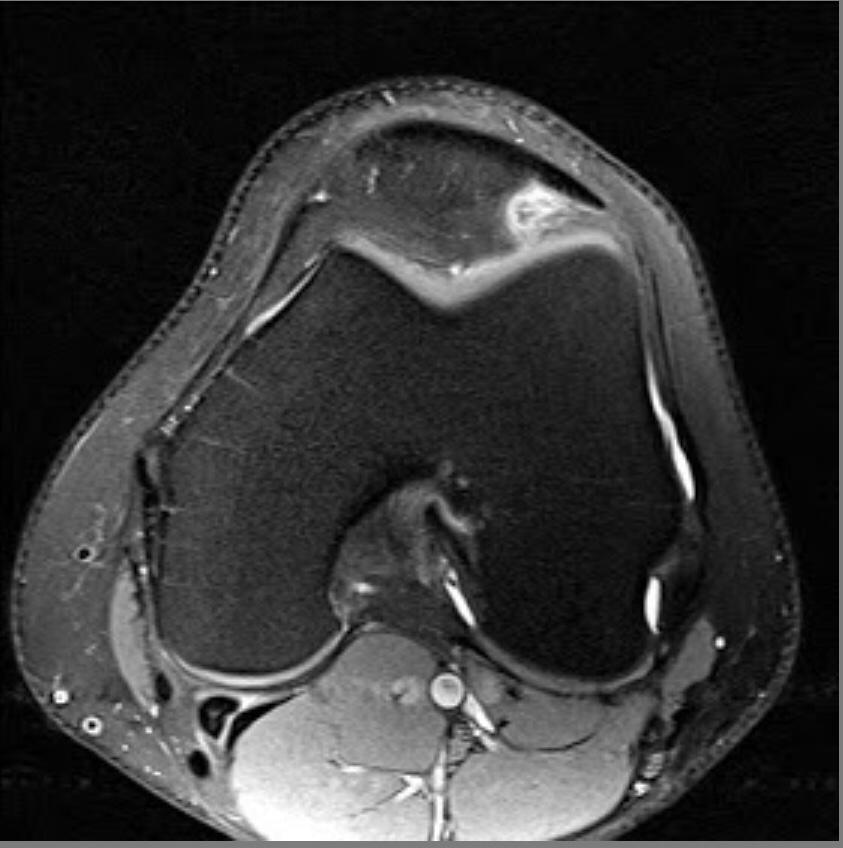

PATELLAR TENDON-LATERAL FEMORAL CONDYLE FRICTION SYNDROME

Patellar tendon-lateral femoral condyle friction syndrome, also known as Hoffa fat pad impingement syndrome, is a common cause of anterior knee pain in active individuals. It is thought to be due to patella maltracking or imbalance of the forces between medial and lateral vastus muscles causing impingement of the superolateral aspect of Hoffa fat pad between the inferior patella and the lateral femoral condyle.

Patients with Hoffa syndrome would present with acute or chronic sharp pain below the patella which is worsened by activities like walking, prolonged standing, wearing high heel shoes or any other activity that puts the knee into full extension. On examination, there may be swelling in the infrapatellar region, with point tenderness at the inferior pole of the patella.

The diagnosis is classically made with MRI and usually occult on radiography and CT. MRI findings include focal area of high T2 signal (edema) at the inferolateral aspect of the patellofemoral joint, within the superolateral portion of the infrapatellar fat pad. A cystic lesion can sometimes be found between the lateral femoral condyle and the lateral retinaculum. Associated findings include lateral patellar subluxation and patella alta (Insall-Salvati ratio greater than 1.2) which are found in around 90% of cases. Conservative treatment is usually successful, although full recovery may take time.